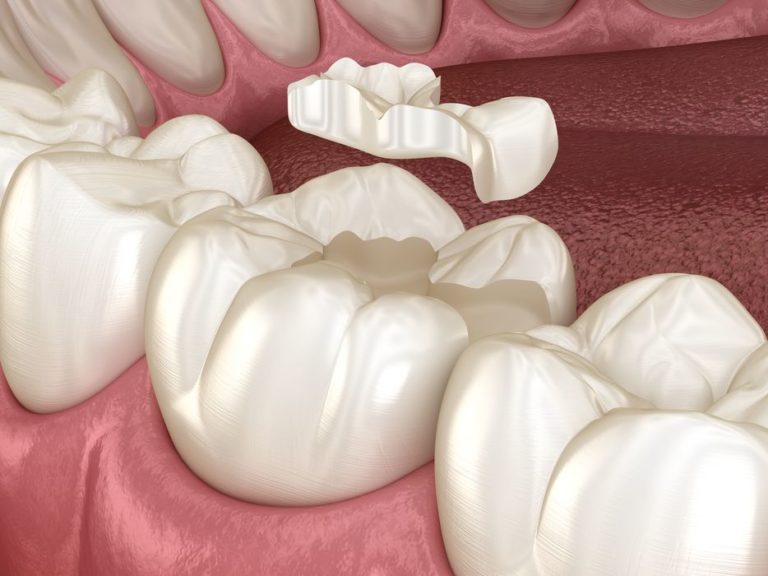

Fijación De La Corona Cerámica Onlay Sobre El Diente Molar. Ilustración Onlay Ceramica It is a more conservative alternative to crowns as it requires less removal of the tooth structure. Porcelain onlays blend seamlessly with the natural tooth color, making them virtually undetectable. Ceramic onlay appears to be a reliable option to restore posterior teeth. This case report discusses the preparation of a functional and aesthetic ceramic onlay for a patient with a. Onlay Ceramica.

Fijación de corona de cerámica onlay sobre diente molar. Ilustración 3D Onlay Ceramica It is a more conservative alternative to crowns as it requires less removal of the tooth structure. This case report discusses the preparation of a functional and aesthetic ceramic onlay for a patient with a cracked tooth. The most common pattern of failure is fracture of the ceramic material. Ceramic onlay appears to be a reliable option to restore posterior. Onlay Ceramica.